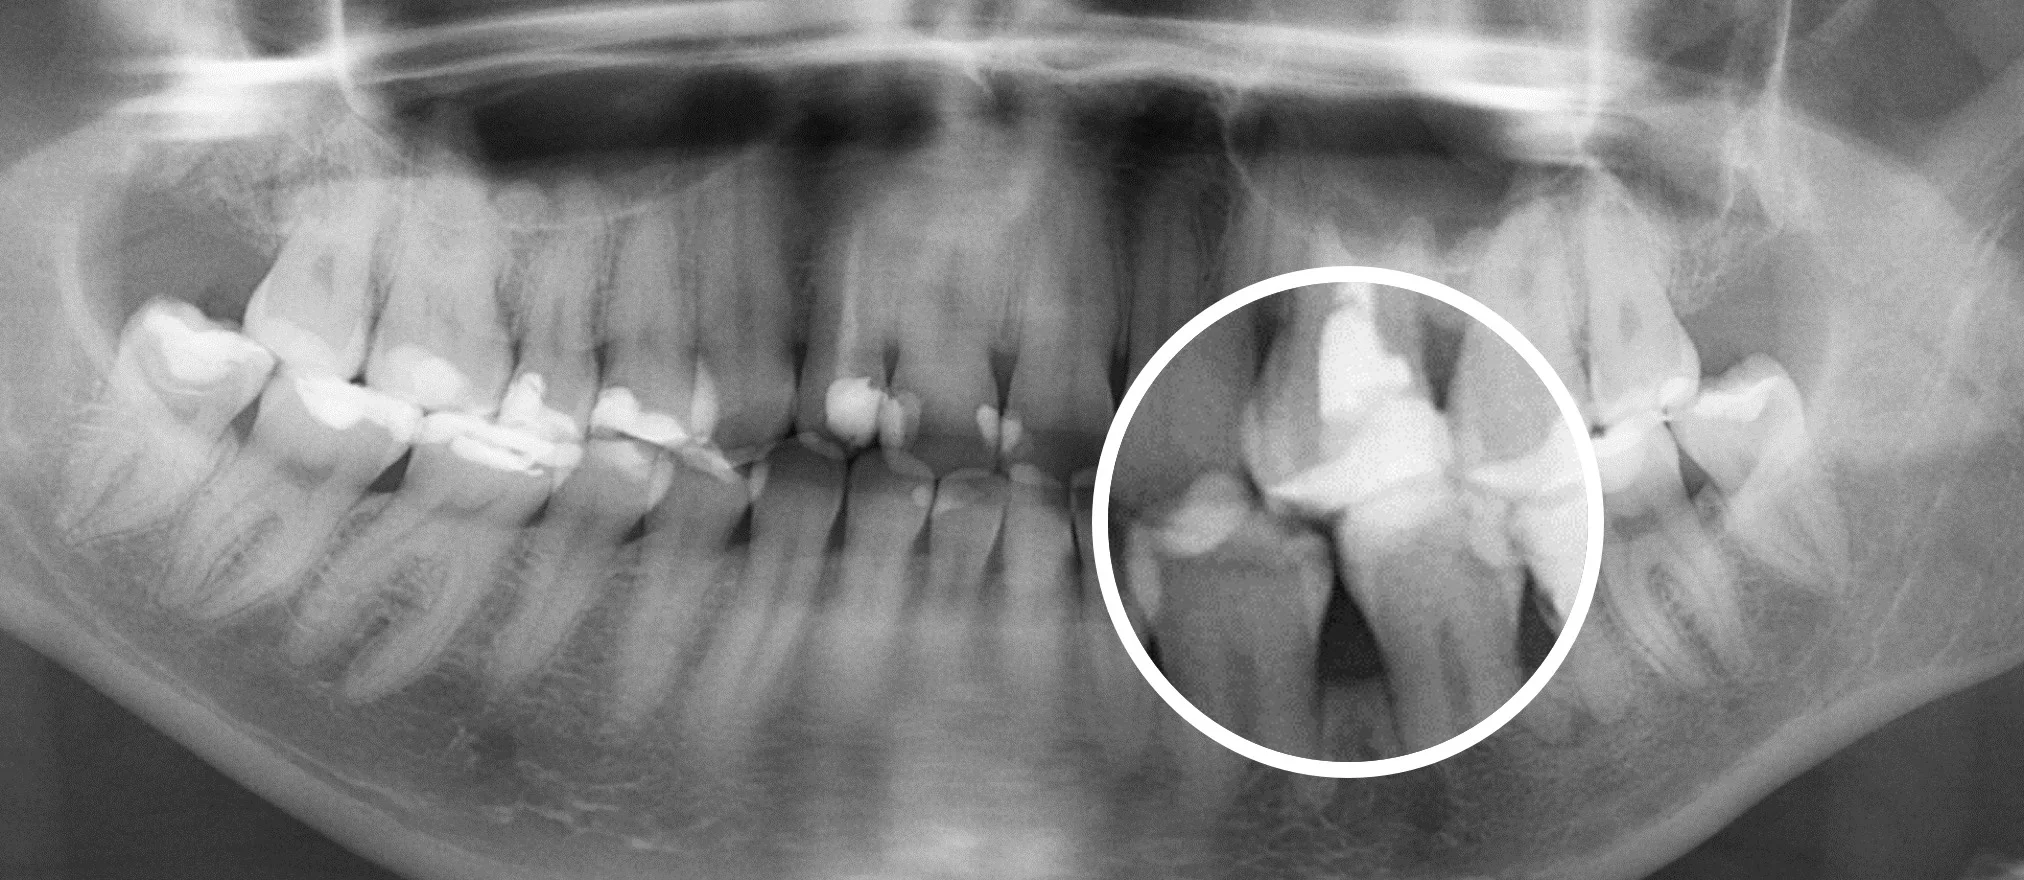

Результат работы искусственного интеллекта

Красным цветом показаны проблемные зубы, синим цветом — зубы с пломбами или ортопедическими конструкциями, белым цветом — здоровые зубы.

Сравнение подходов в изучении 3D снимков